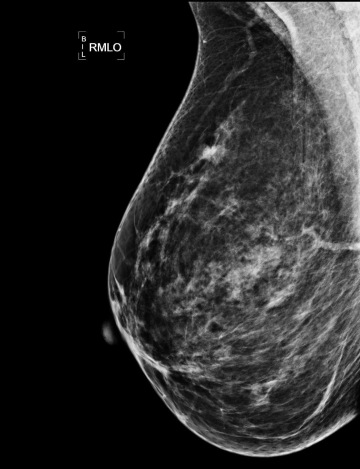

Snímek mamografie s ložiskem nádoru

Na vyšetření mamografem si budeš muset odložit oblečení z horní poloviny těla, včetně podprsenky. Následně tě laborantka doprovodí k RTG přístroji a vestoje ti prs stlačí kompresní deskou. Se vším ti pomohou, nemusíš se bát, ale je důležité jim v tuto chvíli naslouchat! Každý prs se vždy snímkuje dvakrát – tedy ve dvou projekcích – shora dolů a šikmo. Stlačení jako takové může být nepříjemné nebo bolestivě, jde vždy ale jenom o pár vteřin, bez kterých by bohužel snímek nebyl dostatečně kvalitní. ⌚

Pomoci s diagnostikou prsu může také metoda 3D mamografie, tzv. tomosyntéza, neboli DBT (umožní zobrazení tkáně v jednotlivých vrstvách), která slouží často jako doplňkové vyšetření v případě nejasností během screeningu nebo u žen s hustou prsní tkání.

Dalším vyšetřením, které pomáhá s diagnostikou je kontrastní mamografie, tzv. CEM. Při tom dochází k nitrožilnímu podání jodové kontrastní látky, která se následně může hromadit právě třeba v maligním nádoru.